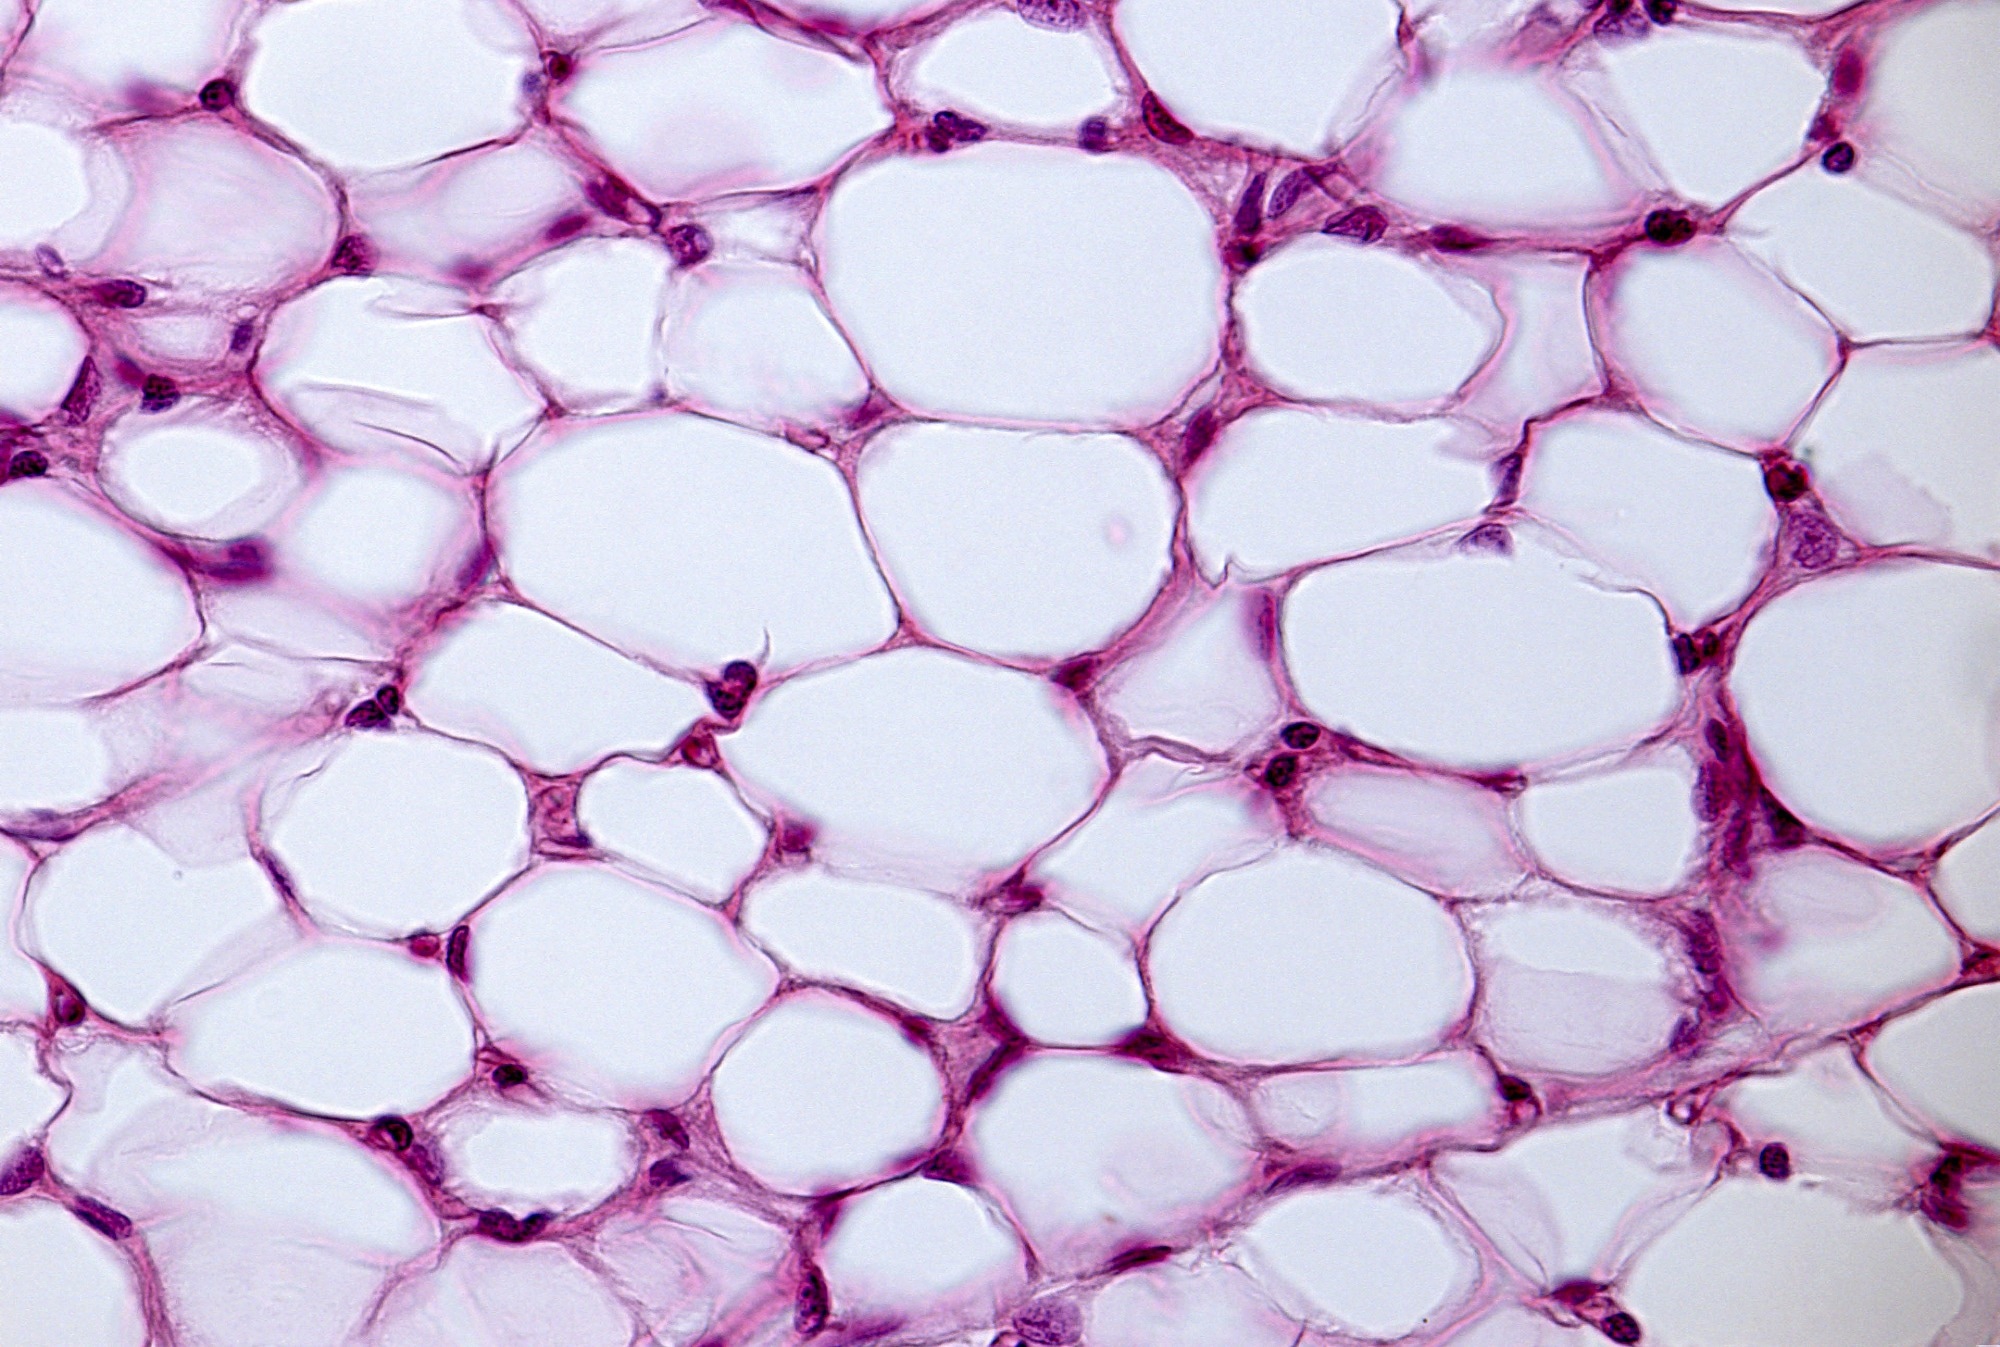

מחקרים חדשים חושפים יתרון מטבולי מרכזי אצל נשים: ברגע שהתמוטטות השומן מתחילה, זה קורה ביעילות רבה יותר מאשר אצל גברים.

מחקר אוסטרלי מרכזי מגלה כי המשקל לטווח הארוך של הילד קשור קשר הדוק ל- BMI של הוריהם לפני הלידה, ובמיוחד